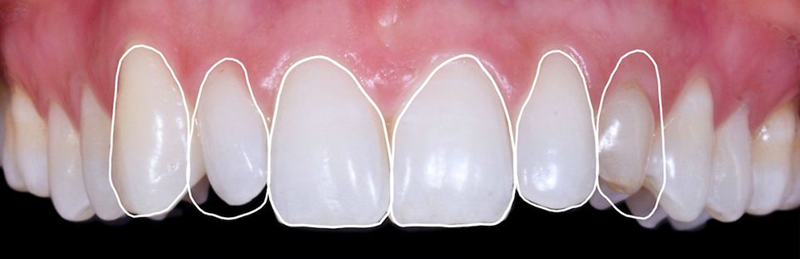

口外检查中,面部评价显示面部对称、比例匀称。微笑分析显示中线矢状面与微笑中线重合,上切牙和尖牙的暴露率为90%(图1)。微笑还显示侧切牙形状不同,与对侧恒尖牙相比,左上乳尖牙更短、更窄、颜色更黄(图2-4)。

Fig. 2: Frontal view of the patient’s smile.

Fig. 6: Intraoral view: The discrepancy between upper canines and lateral incisors is clear. Note that the deciduous tooth is shorter than the contralateral, both at the occlusal and at the gingival side.